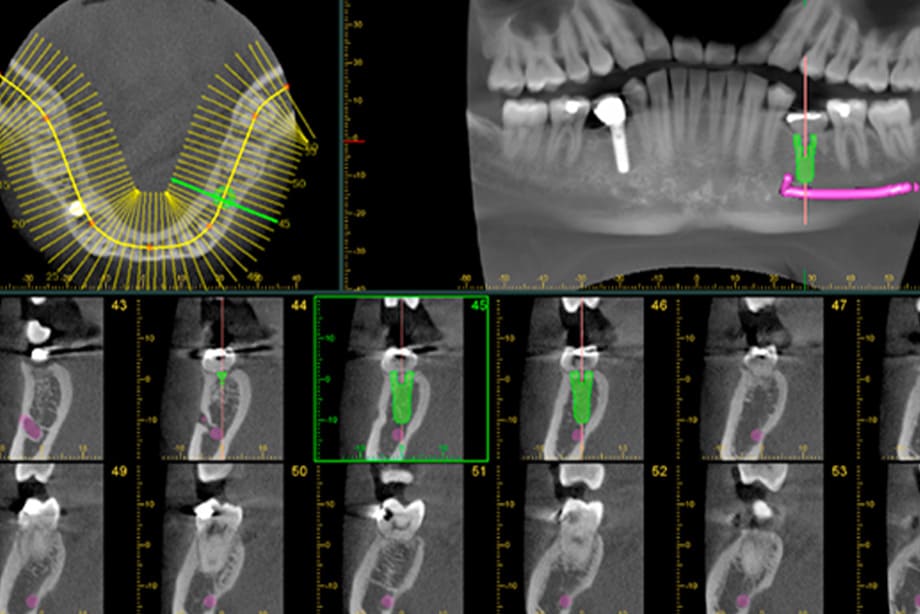

当院で使用するのは、3D撮影が可能な新鋭のレントゲン機械です。

歯、神経、骨の状態を立体的、かつ鮮明に映し出し、平面的なレントゲンよりも精密な診査・診断を行うことができます。 -

現時点でのむし歯や歯周病のリスク、磨き残しや歯並びの特徴など、ご自身では把握しにくいお口の中の状態についても丁寧にご説明します。また、レントゲンで撮影した画像などを一緒に見ながらお話しすることで、患者様にもわかりやすい説明を心がけています。 -